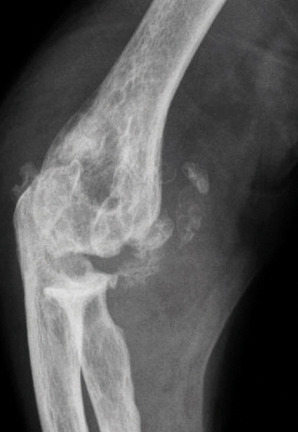

Les radiographies permettent de déceler des modifications ostéocartilagineuses asymétriques (mains, pieds, poignets, coudes, genoux), secondaires à la réaction inflammatoire autour des tophus, comportant :

• des érosions osseuses initiales caractéristiques : encoche épiphysaire (fig. 3) avec un éperon osseux (aspect en hallebarde) ;

• une image d’empreinte dans les parties molles (augmentation de la densité des parties molles dues au tophus) très évocatrice (fig. 4) ;

• un interligne longtemps conservé (contrairement aux autres rhumatismes destructeurs) [fig. 3] jusqu’au stade de goutte chronique et l’absence de raréfaction osseuse périarticulaire permettant de différencier la goutte d’autres arthropathies ; à un stade avancé, la goutte tophacée peut avoir un potentiel destructeur à la fois articulaire et osseux (fig. 4).